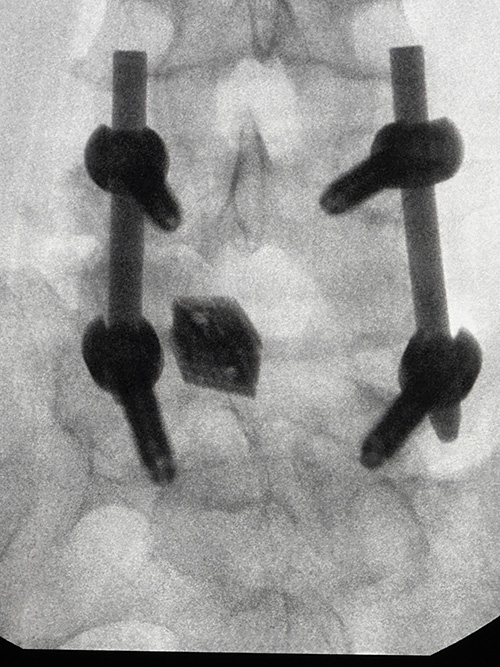

Szpital MSWiA w Kielcach ma na swoim koncie liczne sukcesy, a dr Arkadiusz Granek po raz kolejny przyczynia się do jednego z nich, wykonując – z pełnym sukcesem – jedną z pierwszych w Europie operacji w pełni endoskopowej stabilizacji kręgosłupa odcinka lędźwiowego.

Dzięki tej metodzie chory po wcześniejszej dekompresji L5/S1 z bólem korzeniowym po lewej stronie, obecnie podaje ustąpienie objawów.